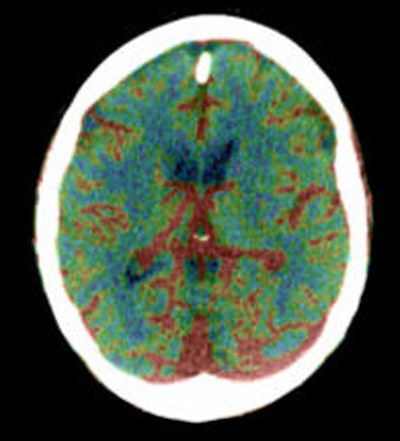

| Diffusion-weighted image as well as fluid-attenuated recovery T2-weighted images obtained two days after the initial perfusion CT and MRI demonstrate a hyperintense area close to that on the perfusion CBF and MTT maps and the initial diffusion-weighted imaging. A slight penumbra loss is demonstrated. Images courtesy of Dr. Sotirios Bisdas. |

![]() |